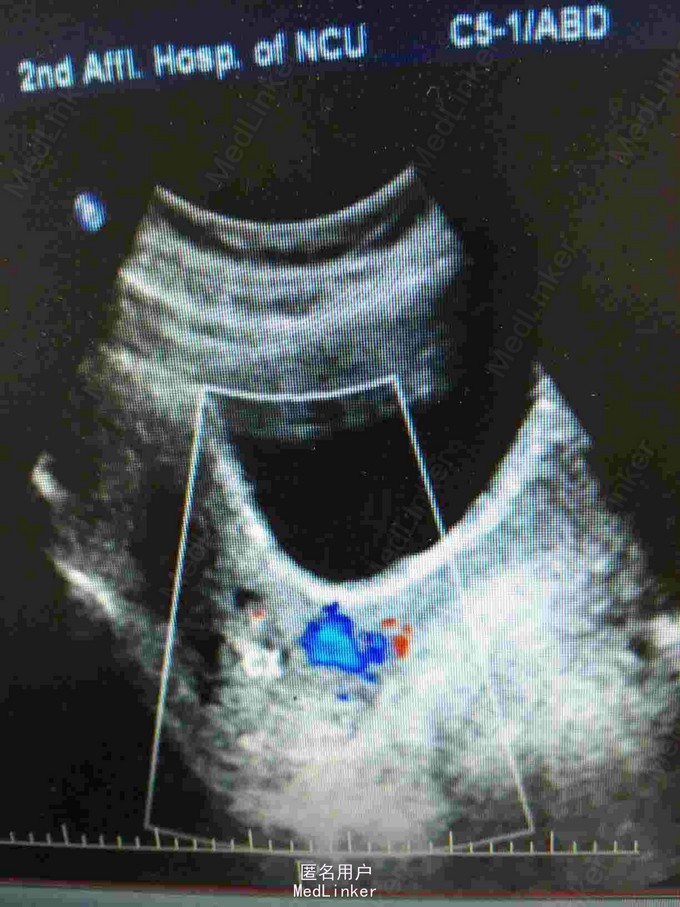

查体:宫颈:前唇菜花样糜烂,接触性出血,后唇光滑;宫体:前位,常大,活动,宫旁软。妇科彩超示:子宫颈体积增大,回声欠均匀,右侧附件区囊性暗区,考虑非赘生物囊肿,